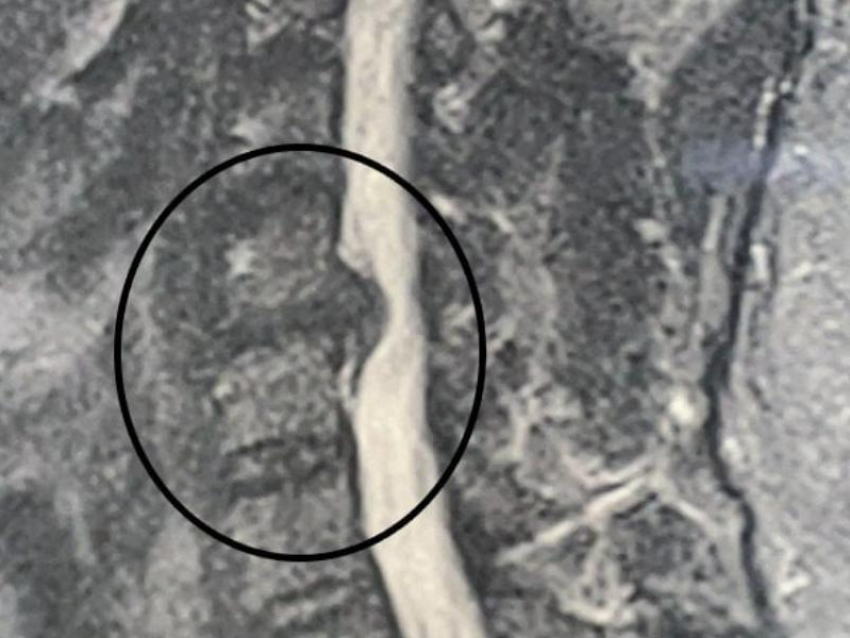

Диагноз звучал серьезно – грыжа межпозвонкового диска на уровне С5-С6, да еще и осложненная. Простыми словами, выпячивание диска сдавило нервные корешки, отвечающие за чувствительность и движение правой руки. Врачи объяснили мужчине весь риск - без хирургического вмешательства болезнь будет прогрессировать и может привести к полному параличу конечности.

Доступ к поврежденному диску осуществлялся через небольшой разрез на передней поверхности шеи — так называемый передний микрохирургический доступ.

Это ювелирная техника, требующая высочайшей точности. С помощью операционного микроскопа и микрохирургических инструментов врачи аккуратно удалили разрушенный диск и саму грыжу, которая сдавливала нервные структуры.

Чтобы сохранить нормальную анатомию и функцию позвоночника, на место удаленного диска установили специальный имплант — межтеловой кейдж. Эта металлическая конструкция, похожая на небольшую распорку, соединяет соседние позвонки, сохраняя высоту межпозвонкового пространства и стабилизируя отдел.